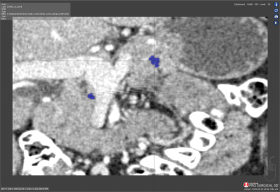

Scan 29: IOU of 6.7

Intersection Over Union (IOU)

IOU is the intersection of the area of the Ground truth and the test segmentation over the area of both the Ground truth and test segmentations.